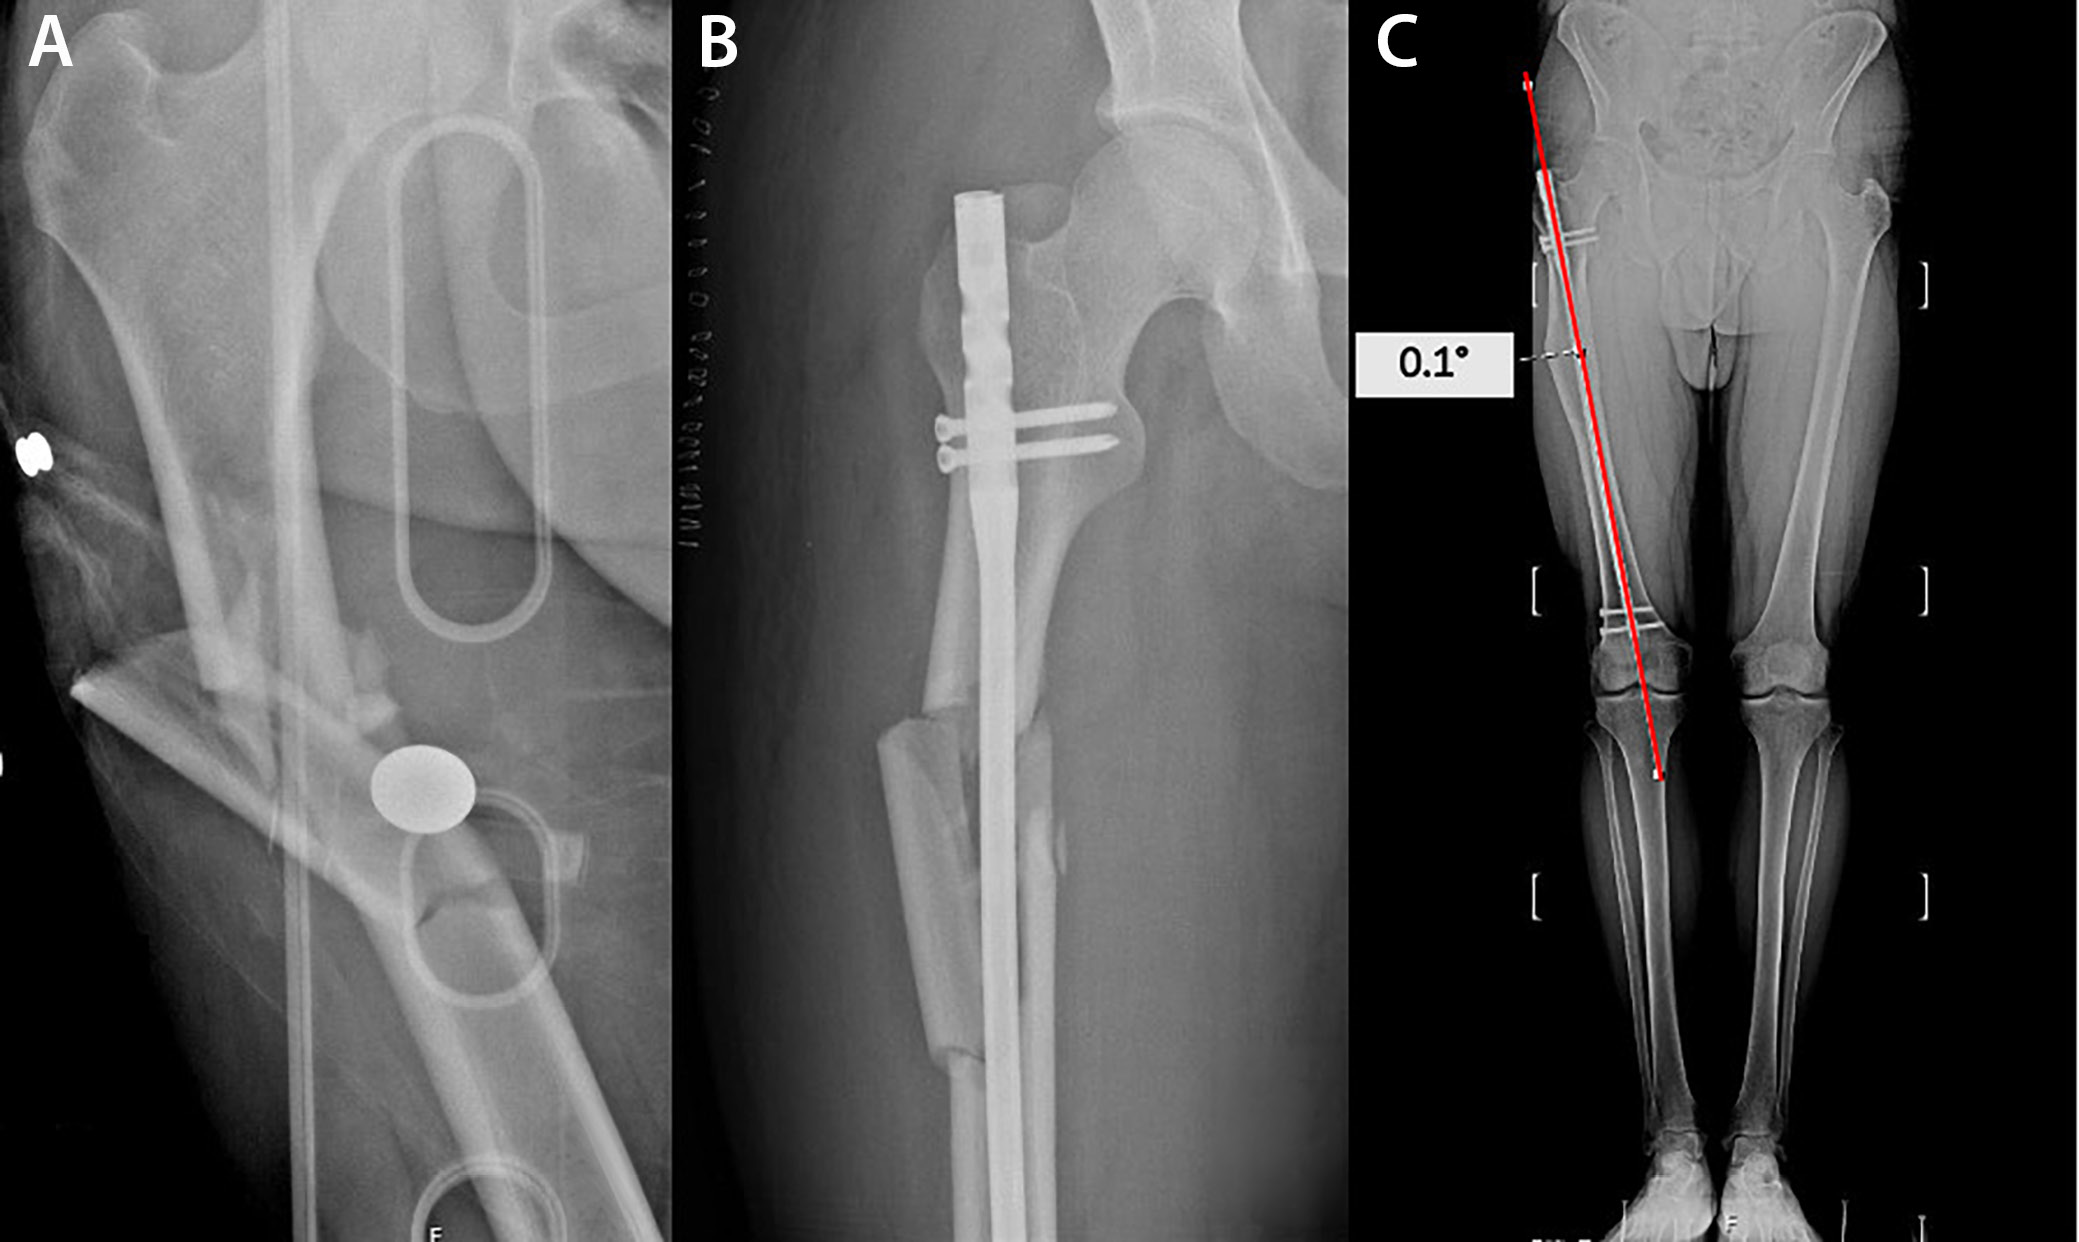

Orthoroentgenograms were used to assess femoral length discrepancies, coronal plane angulations (varus/valgus) at the fracture line, mechanical lateral distal femoral angle (mLDFA), mechanical medial proximal tibial angle (mMPTA), and postoperative lower extremity mechanical axis angle (MA), and to compare the sizes of the lesser trochanters on both sides to detect rotational deformity (Figure 1, Figure 2, Figure 3). Coronal plane deformity of the femur was evaluated by drawing one line from the fracture site to the proximal center of the medullary canal and another line from the fracture site to the midpoint of the distal femoral articular surface. The angle between these 2 lines was then measured (Figure 1C, Figure 2C).

Intramedullary nails were placed through the greater trochanter in 37 patients (30.8%), through the piriformis fossa in 59 patients (49.2%), and laterally to the greater trochanter in 24 patients (20%). A coronal plane deformity ≥5° was observed in 2.7% of patients with intramedullary nails inserted through the greater trochanter, 50% of patients with nails inserted via lateral access to the greater trochanter, and 11.9% of patients with nails inserted through the piriformis fossa. It was determined that coronal plane deformity was more frequent in nails inserted from the lateral side of the greater trochanter. This difference was found to be significant (χ2 = 28.092, p < 0.001) (Table 2).

The incidence of coronal plane deformities ≥5° in this study aligns with previous findings, in which deformities above 5° are reported in 2–18% of cases after locked IMN.9, 11, 13 Notably, we observed a significantly higher rate of coronal deformities when the nail was inserted laterally to the greater trochanter compared to other insertion points. This result suggests that the choice of nail insertion point may influence postoperative alignment, which could have implications for surgical planning.

Lateral entry points likely alter the trajectory of the nail, making precise alignment more challenging, especially in cases of complex fracture patterns resulting from high-energy trauma. Our findings are consistent with earlier reports suggesting a strong correlation between lateral insertion points and increased varus or valgus angulations.14 Sadagatullah et al. concluded that there was a higher rate of malalignment in proximal femoral shaft fractures treated with interlocking nails utilizing the greater trochanter entry point.15 Similarly, Ostrum et al. reported that a lateral starting point led to malalignment and gapping of the femoral cortex with all nails.16